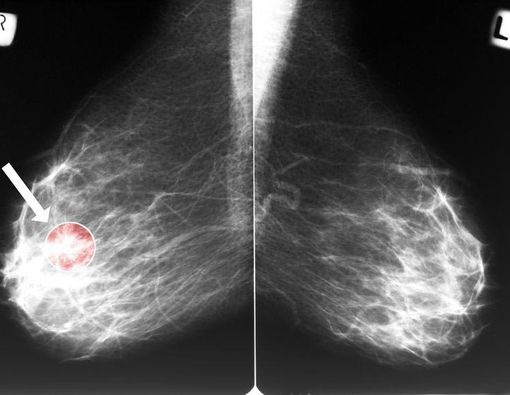

Benjolan fibroadenoma ini dapat diketahui melalui pemeriksaan SADARI jika ukurannya cukup besar untuk diraba, atau melalui pemeriksaan mamografi jika ukurannya terlalu kecil dan tidak teraba pada pemeriksaan fisik.